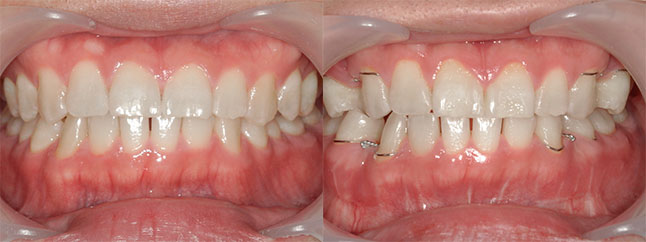

奈良県 20歳 女性

執刀医 辻和志

【治療内容】上下のアゴが前に出ていたため、上下のアゴの骨を切って後ろにさげました。

【費用】上下セットバック 2,307,800円(税込)

【リスク】全身麻酔で行うため全身の健康状態が悪い方は行うことができません。また、手術当日は安静にしていただく必要があります。